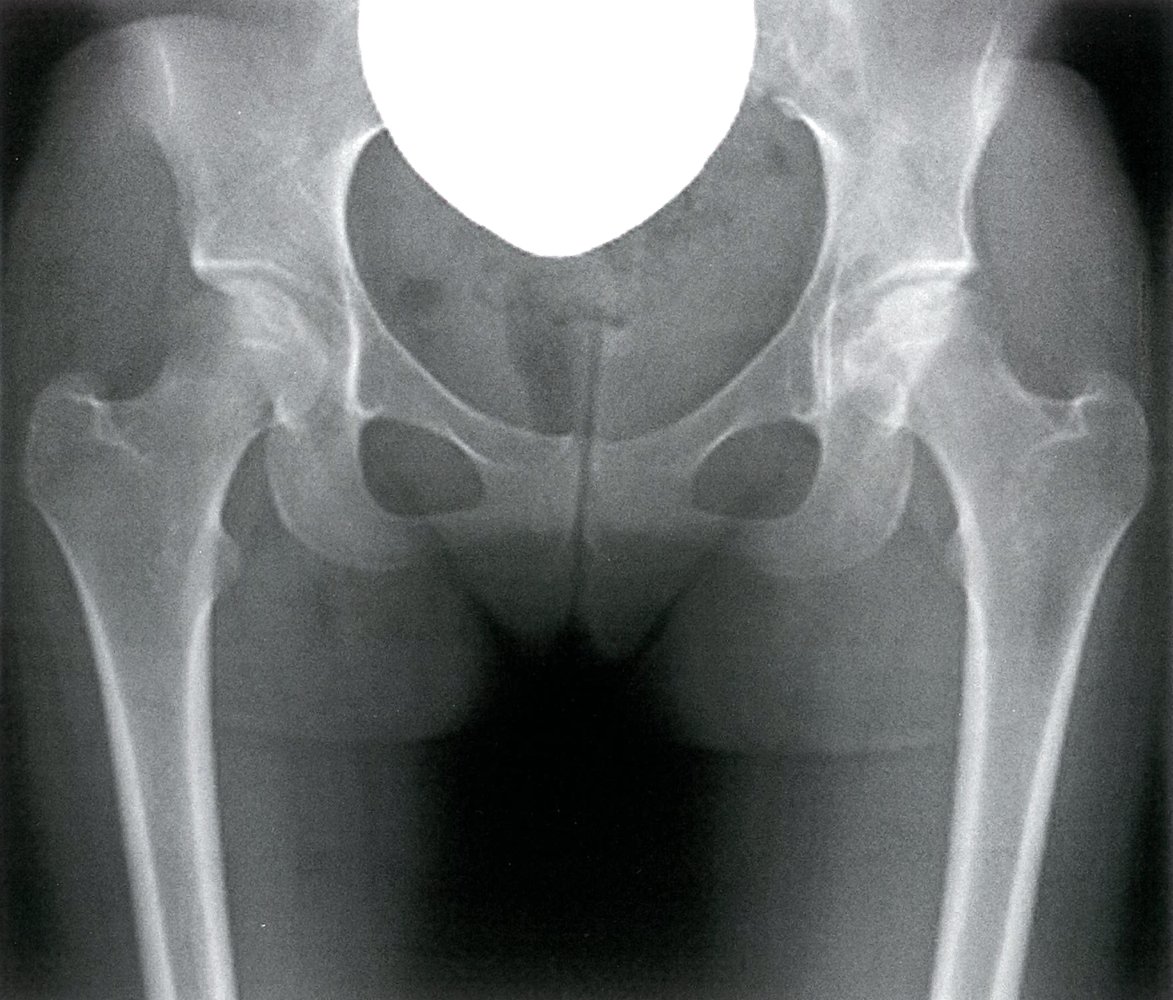

Avascular Necrosis of Femoral Head (AVN) Understanding, Diagnosis, and

Figure 1 from Risk Factors for Avascular Necrosis of the Femoral Head What Causes Avascular Necrosis Risk Factor Upper arm (humerus) and shoulders. Risk factors include alcohol abuse, trauma, steroid use, and connective tissue disorders. Avascular necrosis may be the result of the following: Hip osteonecrosis, also known as avascular necrosis of the hip, represents a condition caused by reduced blood flow to the femoral head secondary to a variety of risk factors such as a. The main. What Causes Avascular Necrosis Risk Factor.